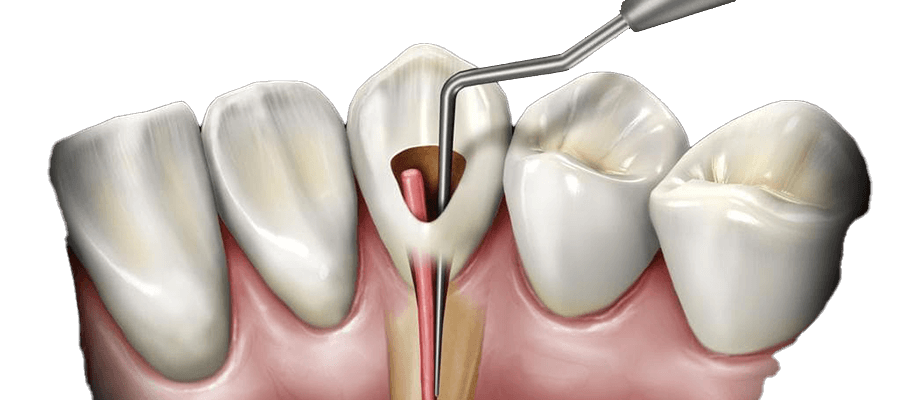

- تشخیص و تصویربرداری : در ابتدا، پزشک نیاز به تشخیص دقیق علت درد و مشکلات دندان دارد. این ممکن است شامل تصویربرداری مانند ایکسری دندان و جوانه دندان باشد.

- از بین بردن بافت مرده : پس از تشخیص، در مرحله بعدی بافت مرده و بافت آسیب دیده از دندان باید از بین برود تا به عفونت پایان داده شود.

- پر کردن فضای خالی : پس از تمیز کردن داخل دندان، فضای خالی با مواد ترمیمی پر میشود. این مواد معمولاً از نوع رزینهای کامپوزیت یا آمالگام است.